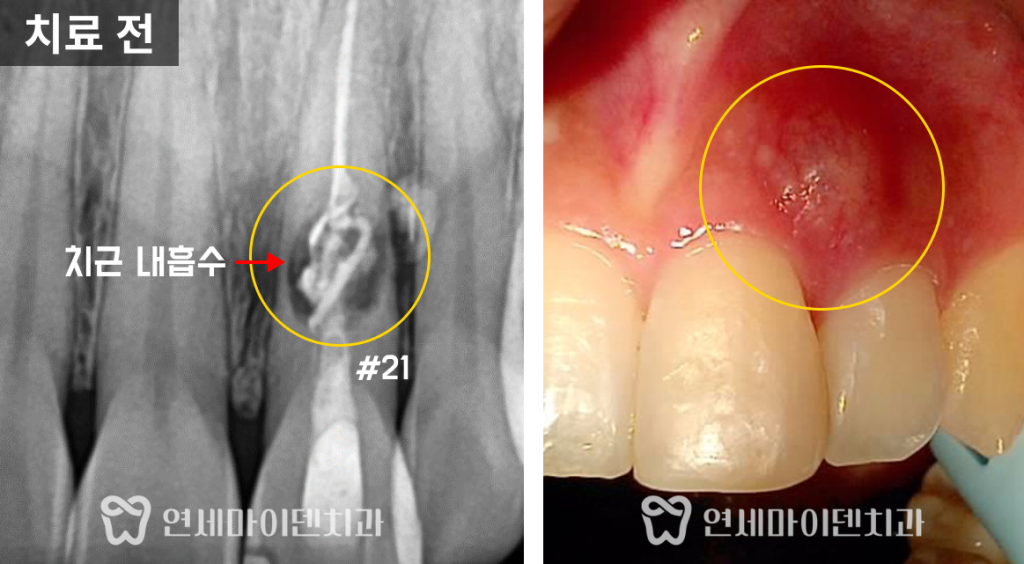

신경치료를 하는 도중 치근 내흡수를 발견했고,

내흡수된 공간을 채우려고 실러를 주입했다고 합니다.

하지만, 주입된 약제는 밖으로 새버렸는데요,

이미 치근내흡수가 많이 진행되어 뿌리에 구멍이 났기 때문입니다.

치근 내흡수란 치아의 뿌리 내부가 흡수되는 질환입니다.

흡수가 진행되면서 치아 뿌리가 점차 얇아지거나

심한 경우 뿌리에 구멍이 생기게 됩니다.

환자분의 치아 방사선 사진을 살펴보면

뿌리쪽 뼈가 까맣게 녹았고, 옆쪽으로 빠져나간 약제도 보입니다.